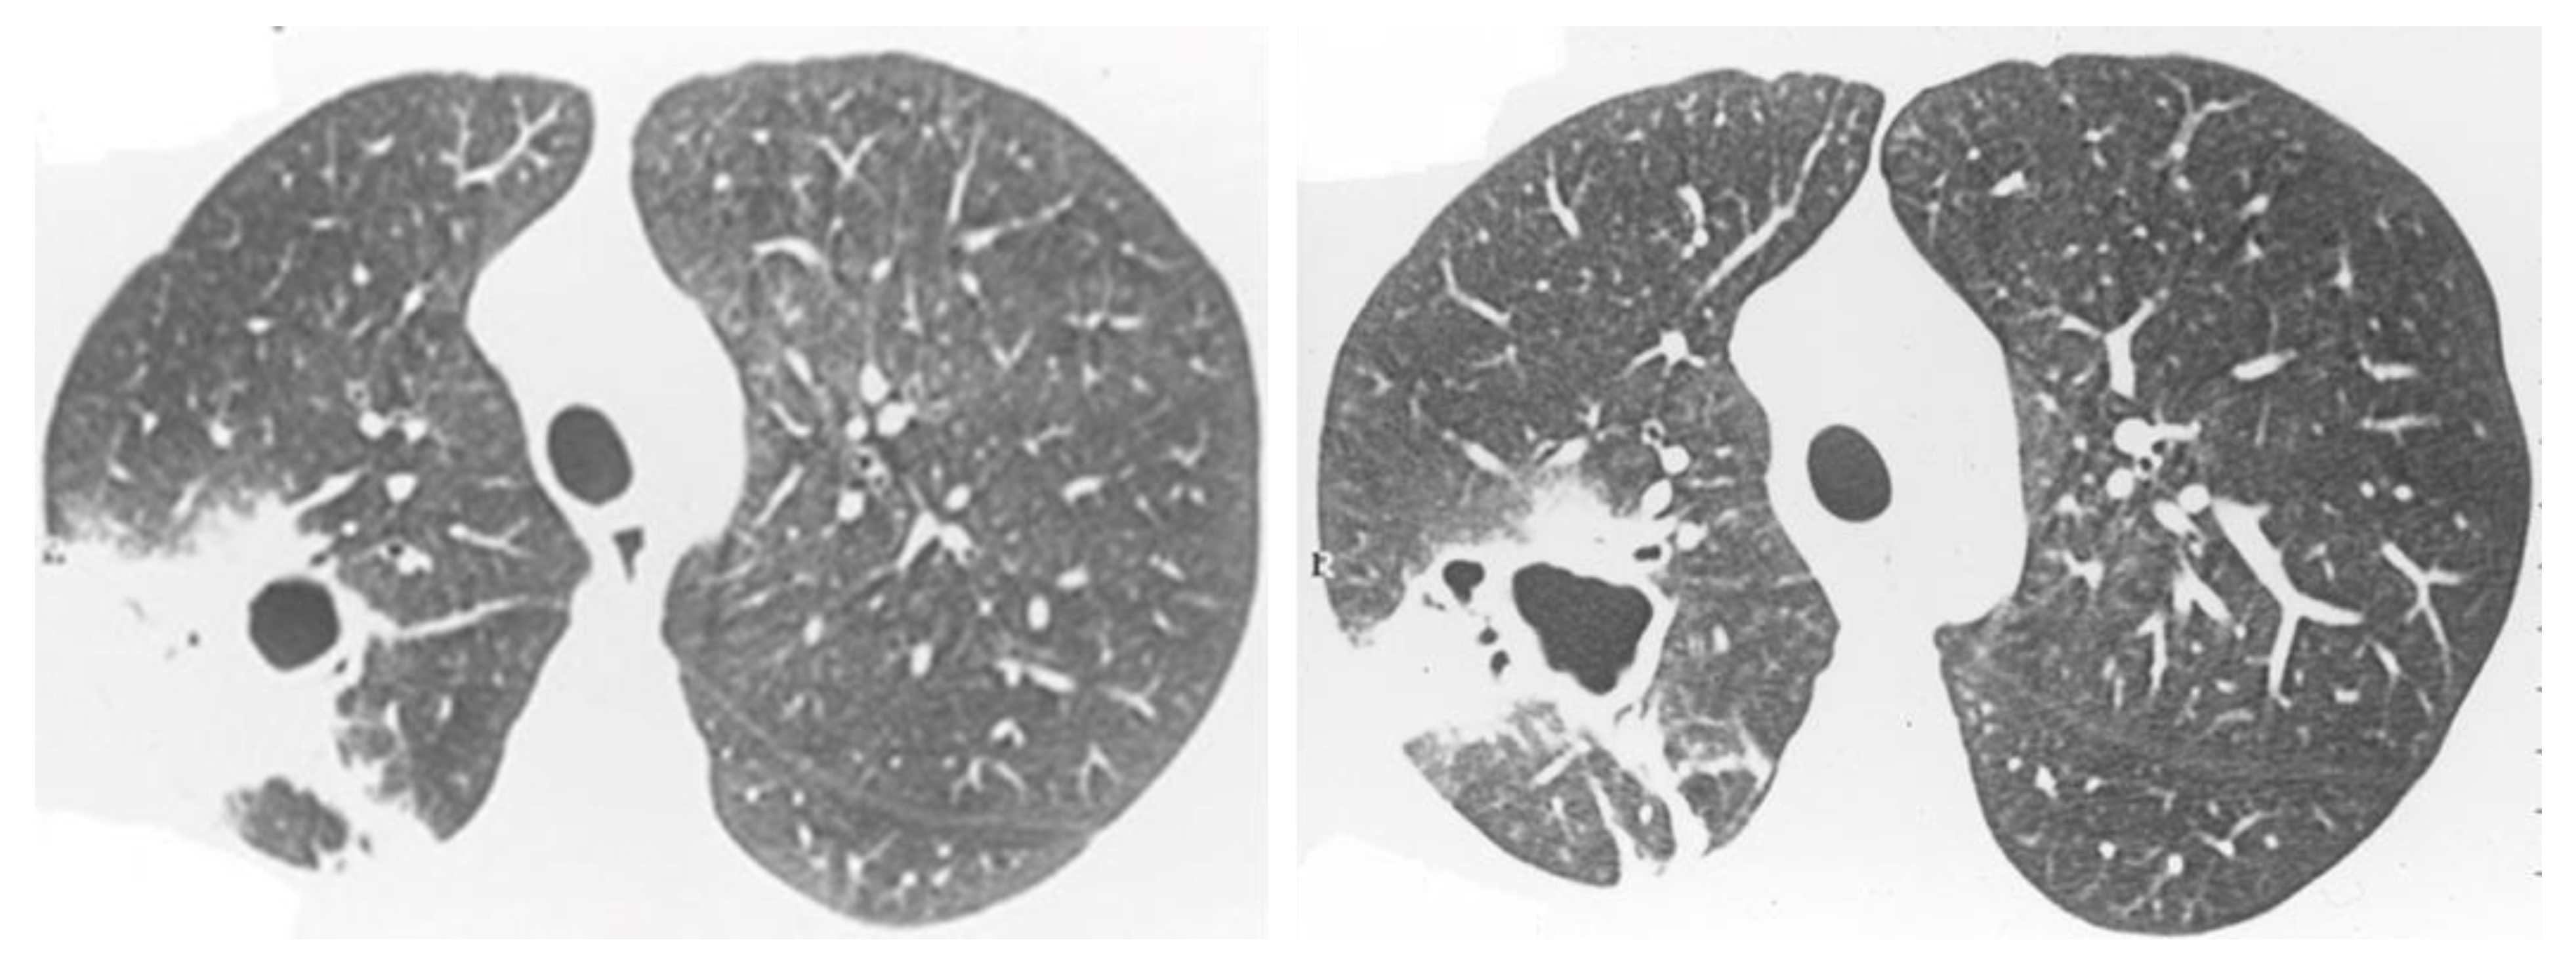

2.2. Non-Resolving Pneumonia

2.5. Mixed Pattern